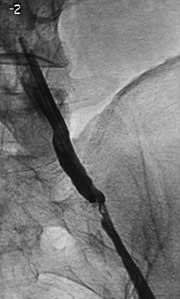

Рис. 4. Контрольная артериограмма после предилатации.